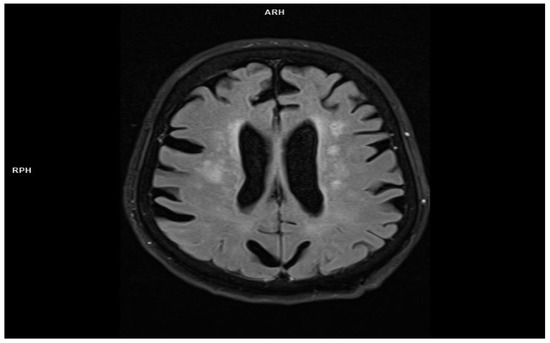

2.2. Patient 2